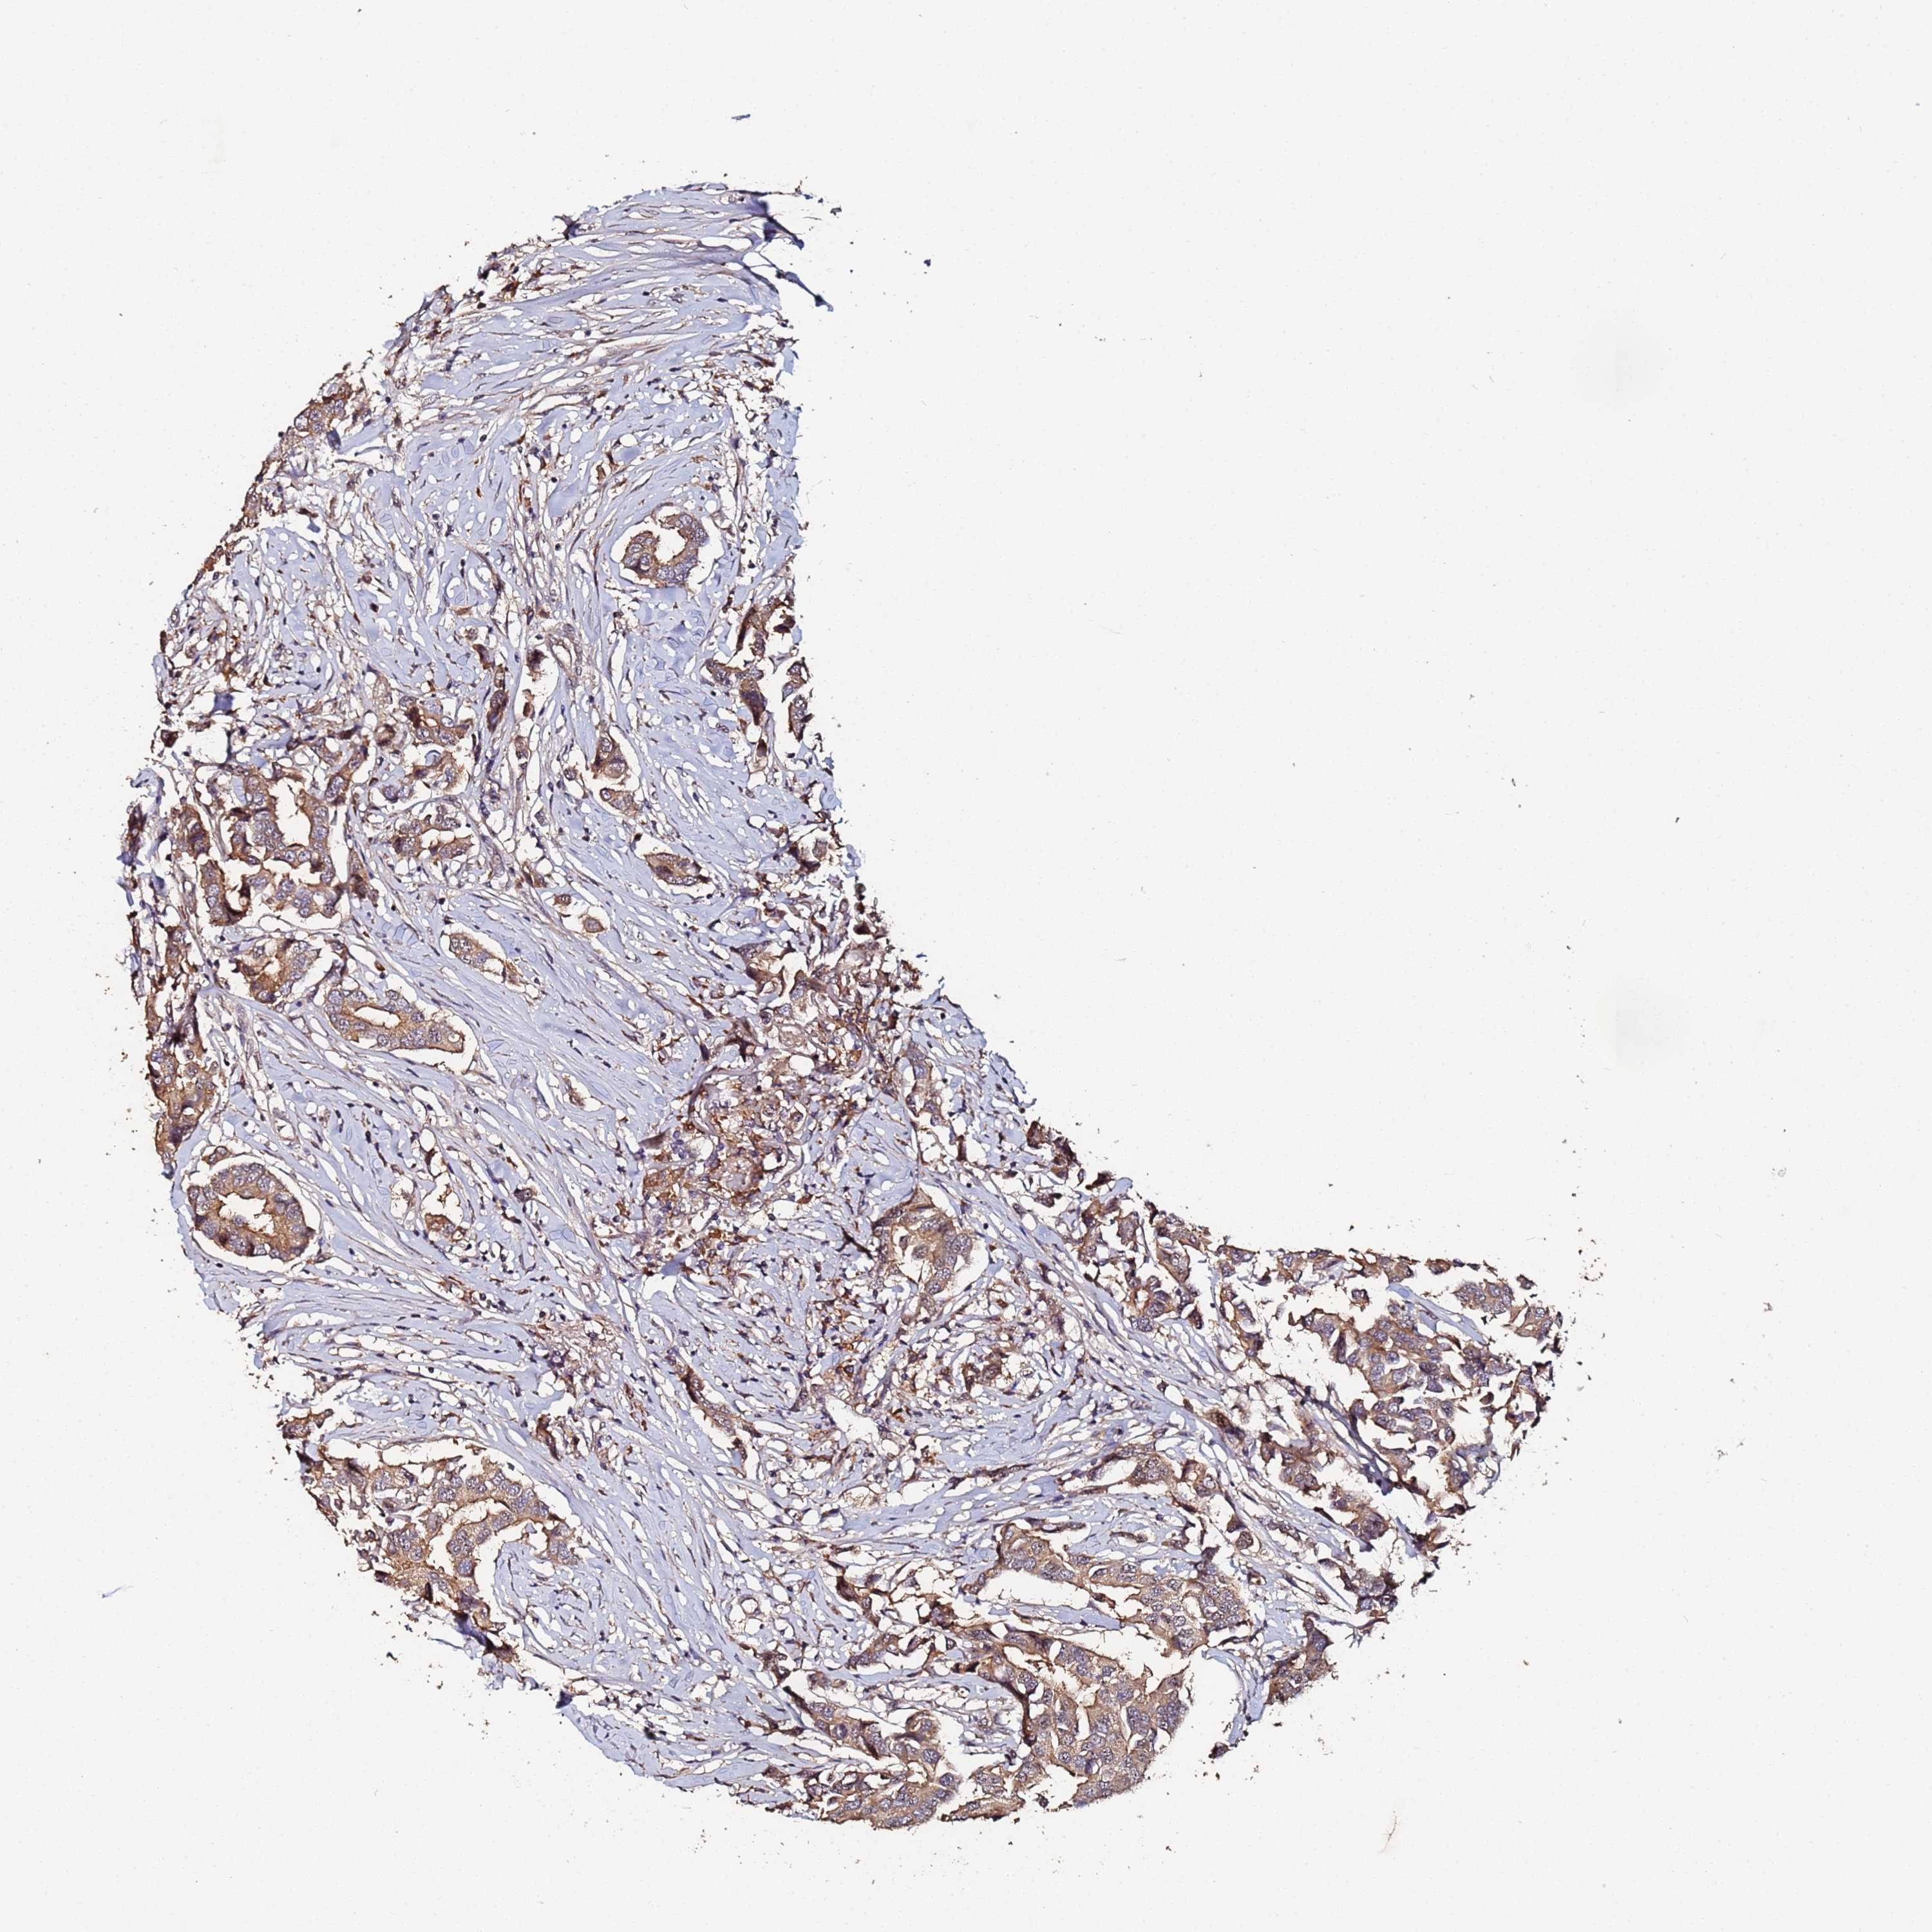

CANCER BREAST CANCER Show tissue menu

BRCA TCGA BRCA VALIDATION PROTEIN EXPRESSION